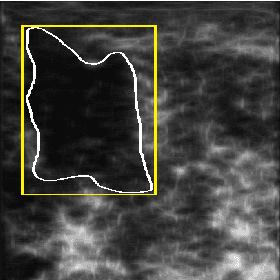

Abstract:Recent advances in using quantitative ultrasound (QUS) methods have provided a promising framework to non-invasively and inexpensively monitor or predict the effectiveness of therapeutic cancer responses. One of the earliest steps in using QUS methods is contouring a region of interest (ROI) inside the tumour in ultrasound B-mode images. While manual segmentation is a very time-consuming and tedious task for human experts, auto-contouring is also an extremely difficult task for computers due to the poor quality of ultrasound B-mode images. However, for the purpose of cancer response prediction, a rough boundary of the tumour as an ROI is only needed. In this research, a semi-automated tumour localization approach is proposed for ROI estimation in ultrasound B-mode images acquired from patients with locally advanced breast cancer (LABC). The proposed approach comprised several modules, including 1) feature extraction using keypoint descriptors, 2) augmenting the feature descriptors with the distance of the keypoints to the user-input pixel as the centre of the tumour, 3) supervised learning using a support vector machine (SVM) to classify keypoints as "tumour" or "non-tumour", and 4) computation of an ellipse as an outline of the ROI representing the tumour. Experiments with 33 B-mode images from 10 LABC patients yielded promising results with an accuracy of 76.7% based on the Dice coefficient performance measure. The results demonstrated that the proposed method can potentially be used as the first stage in a computer-assisted cancer response prediction system for semi-automated contouring of breast tumours.

Abstract:Quantitative ultrasound (QUS) methods provide a promising framework that can non-invasively and inexpensively be used to predict or assess the tumour response to cancer treatment. The first step in using the QUS methods is to select a region of interest (ROI) inside the tumour in ultrasound images. Manual segmentation, however, is very time consuming and tedious. In this paper, a semi-automated approach will be proposed to roughly localize an ROI for a tumour in ultrasound images of patients with locally advanced breast cancer (LABC). Content-based barcodes, a recently introduced binary descriptor based on Radon transform, were used in order to find similar cases and estimate a bounding box surrounding the tumour. Experiments with 33 B-scan images resulted in promising results with an accuracy of $81\%$.